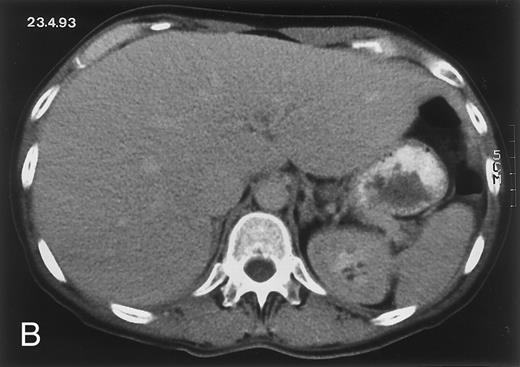

Radiologic evolution in patient A. (A) Postcontrast abdominal CT scan on March 16, 1993 shows multiple small hypodense areas in all segments of the liver, suggestive of hepatic candidiasis. Seven days previously, the patient had recovered from severe neutropenia after the first cycle of chemotherapy for AML. (B) On April 23, 6 days after the neutrophil count had dropped below 500/μL in the second cycle of chemotherapy, there is no evidence of focal lesions on postcontrast CT scan. (C) On June 18, when neutrophils were normalized for 46 days, CT scan again shows multiple small abscesses.